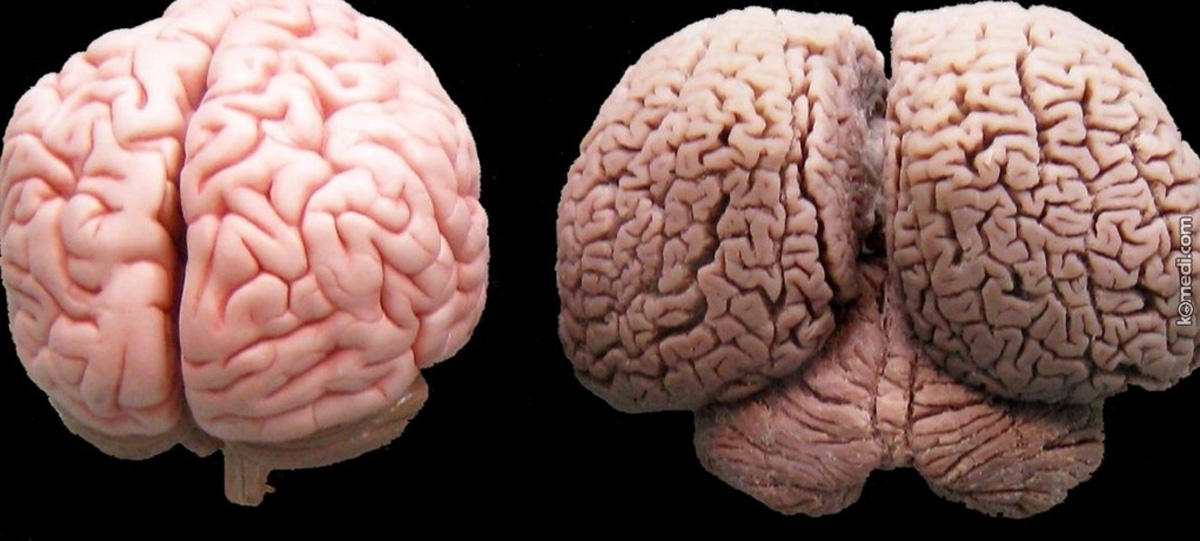

1.Те, которые связаны с поражением головного мозга, например черепно-мозговая травма, его онкологические заболевания и инсульт;

4.Хроническое злоупотребление алкоголем, табакокурением, седативными лекарственными препаратами и тяжелыми наркотиками.

5.Изменения, связанные с возрастом.